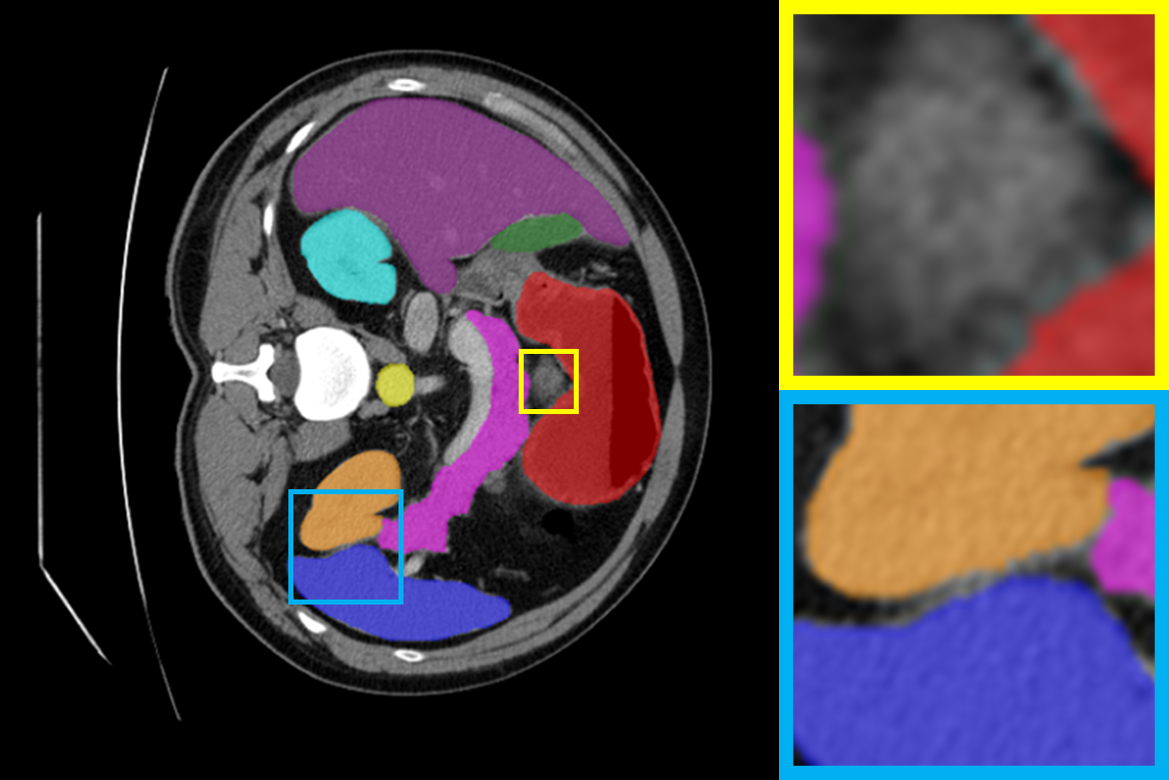

4.3.2 Visual Comparisons

Visualization of our method on the Synapse and ACDC datasets is shown in Fig. 3(a) and Fig. 3(b). For the Synapse dataset illustrated in Fig. 3(a), FCT failed to accurately segment SM and GB, while MERIT achieved precise segmentation of SM but struggled with GB. In contrast, our method achieved accurate segmentation of both SM and GB. Regarding the ACDC dataset shown in Fig. 3(b), while previous methods achieve comparable segmentation of the Myo and LV to the GT, they exhibit noticeable errors on the RV, including invasion into adjacent organs and misrecognition. On the other hand, our method accurately segments across all three structures Myo, LV, and RV, performing as precisely as the GT. We demonstrate the superiority of our method quantitatively and qualitatively.

To demonstrate the superiority of our method, additional qualitative comparison results for the ACDC and Synapse datasets are presented in Fig. 6, Fig. 7, respectively. Notably, in the case of GB, the quantitative results in Fig. 7 show relatively lower performance in ‘only ’. However, the visualization results in Fig. 7 reveal instances where the enhanced images identified GB regions that the original images failed to segment, albeit with some boundary over-segmentation. In such scenarios, our proposed method successfully leveraged the information from enhanced images to achieve more accurate GB segmentation. Note that this finding underscores the fact that even when quantitative performance metrics appear lower, the additional information provided by enhanced images can be valuable in the actual segmentation process.